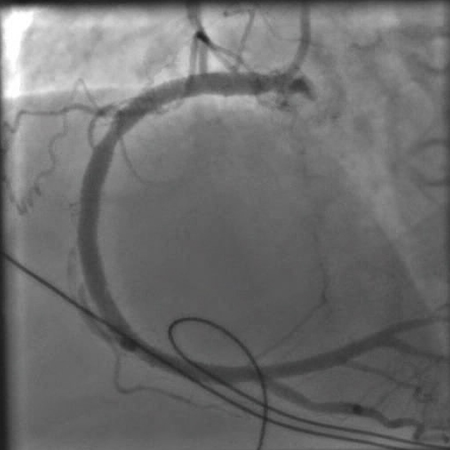

[Figure caption and citation for the preceding image starts]: Angiografia mostrando a artéria coronária direita obstruídaDo acervo pessoal do Dr. Mahi Ashwath; usado com permissão [Citation ends].